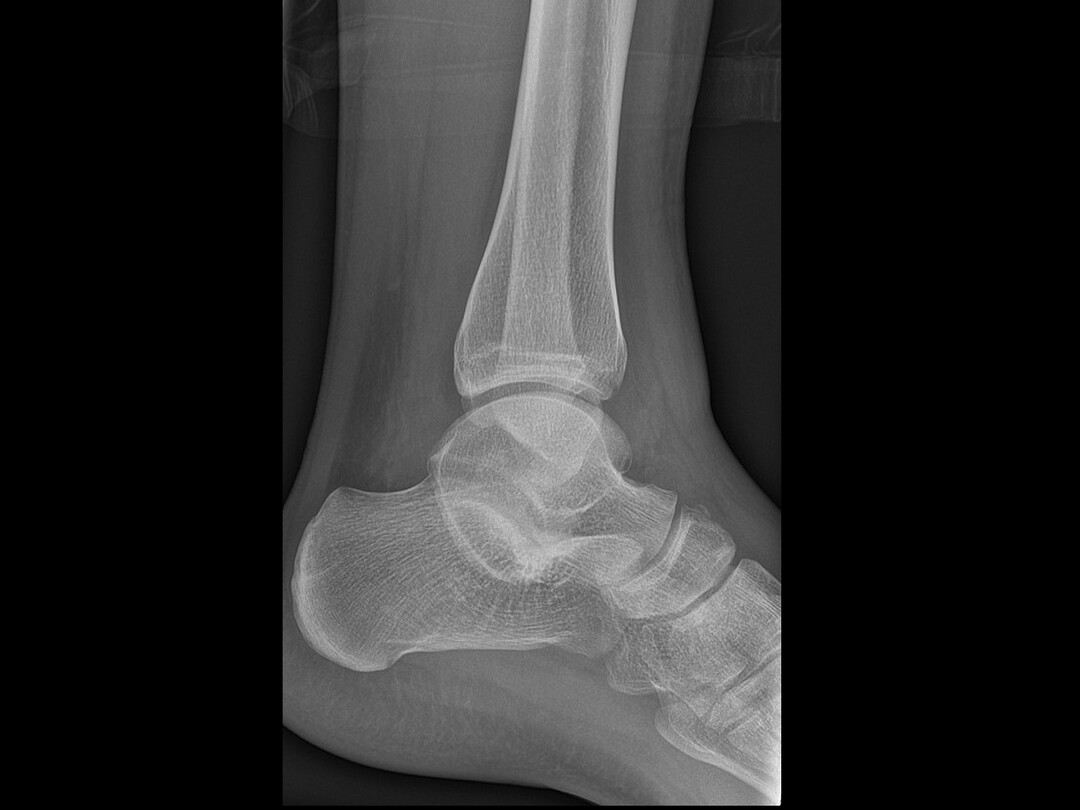

Jaarlijks worden in Nederland naar schatting honderdduizenden patiënten behandeld voor een acute enkelverzwikking op de Spoedeisende Hulp (SEH), bij de huisarts of de huisartsenpost.1 Hoewel het merendeel van deze letsels goed te diagnosticeren en te behandelen is, bestaat er een kans dat een onderliggende afwijking of een afwijkend beloop over het hoofd wordt gezien.2,3 Een voorbeeld hiervan is een gebroken of een door trauma acuut symptomatisch geworden tarsale coalitie.

Een tarsale coalitie is een genetisch bepaalde, abnormale verbinding tussen twee of meer tarsale botten.4 Deze afwijking kan symptomen nabootsen die sterk lijken op een reguliere enkelverzwikking. De…